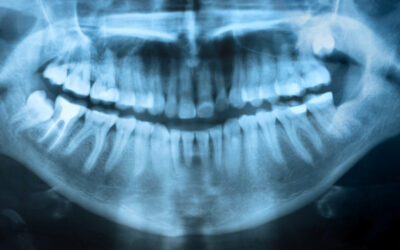

When to Extract Wisdom Teeth

Feb 16, 2017 | Oral Health, Oral Surgery

Wisdom teeth come in last, between 17-25 years of age. If there is enough space in the jaw for these third molars, you can make full use of them. On the other hand, they may be impacted, squeezed beneath the second molars, leading to pain and damage to surrounding...